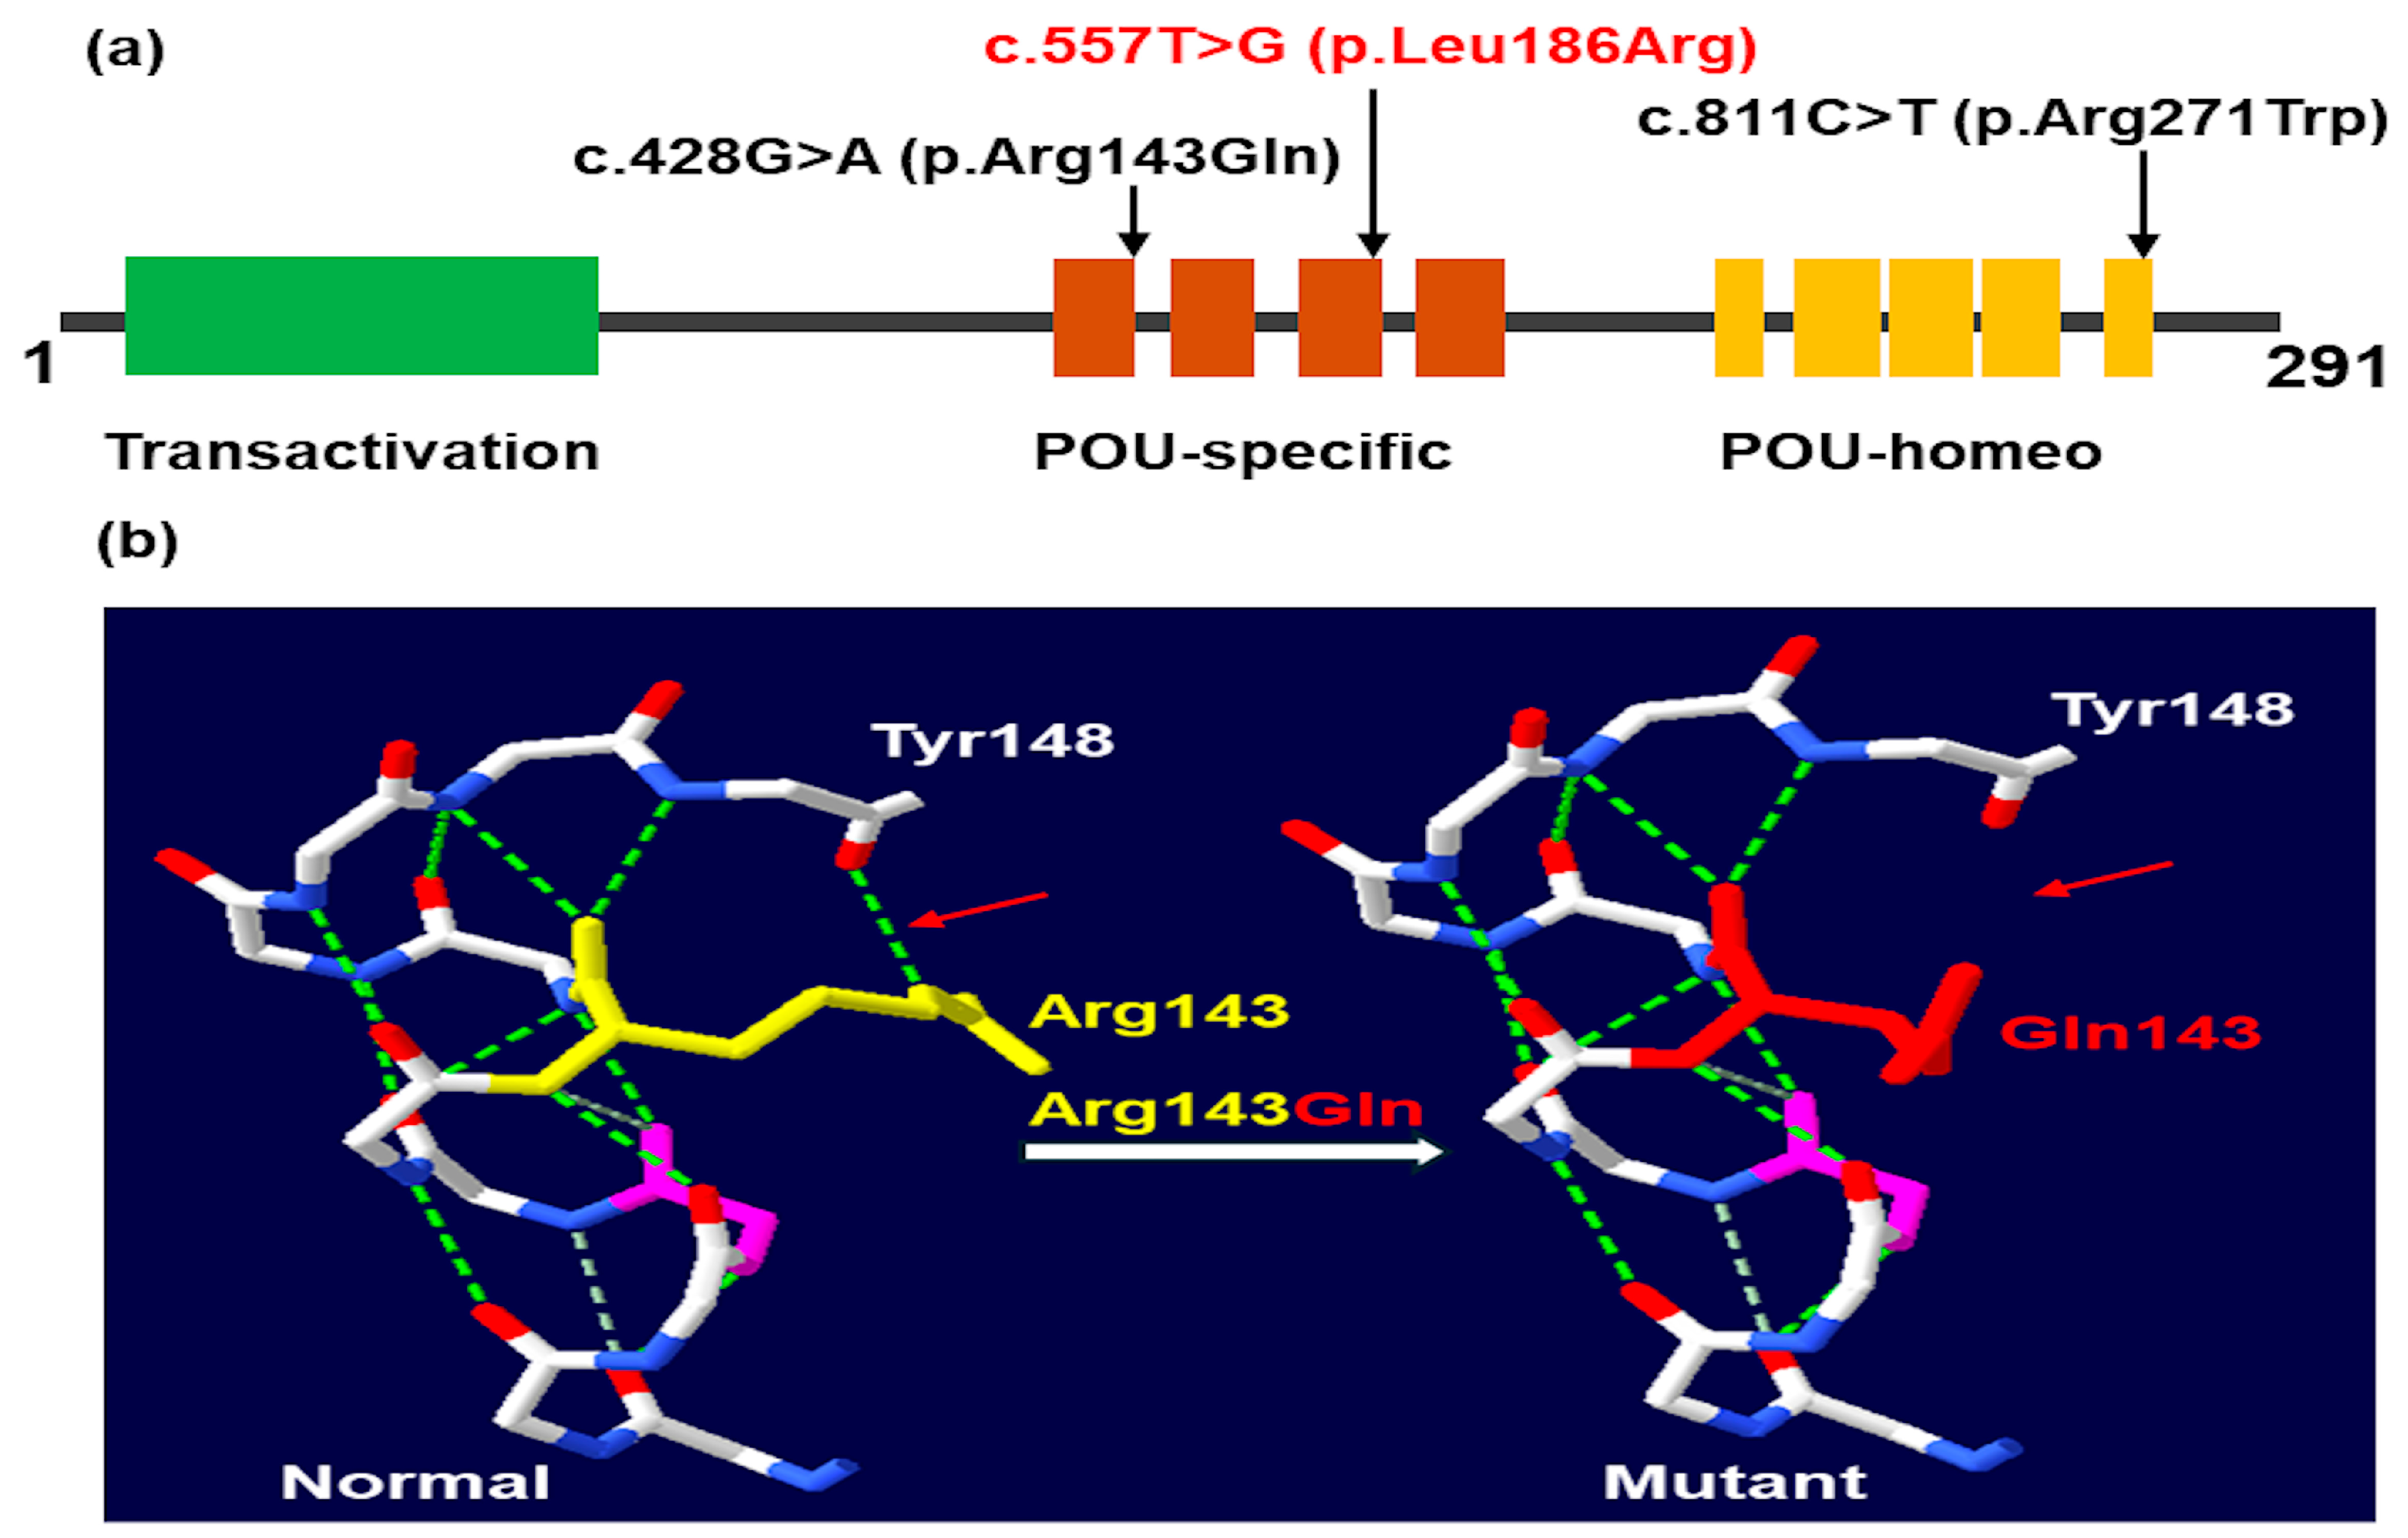

2.2. Molecular Findings

3. Discussion